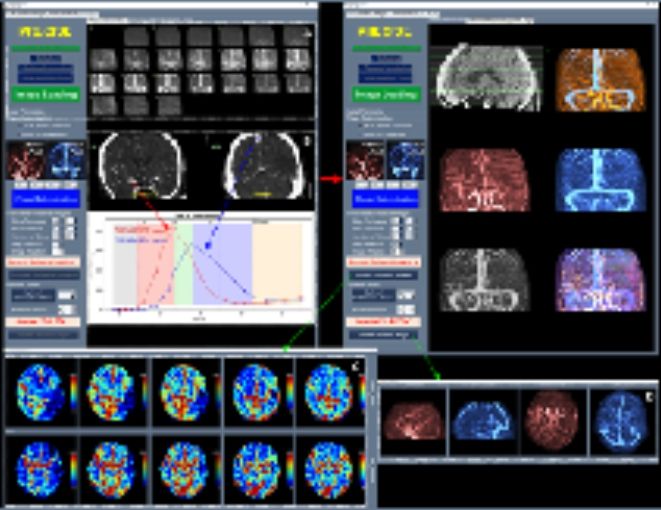

특히 2025년에는 생성형 AI 기술을 활용한 의료기기가 혁신의료기기로 처음 지정됐다. 해당 제품은 흉부 X-ray 영상을 분석한 뒤 42종의 흉부 질환 및 영상 의학적 소견에 대한 판독 소견서(초안)를 자동 생성하여, 영상의학과 전문의의 진단 결정을 보조하는 의료기기이다.

이와 함께 허혈성 뇌혈관 질환 환자를 대상으로 혈관재개통 치료가 필요한 환자 선별을 지원하는 소프트웨어 등 다양한 진단·치료 보조 AI 의료기기들이 혁신의료기기로 지정됐다.